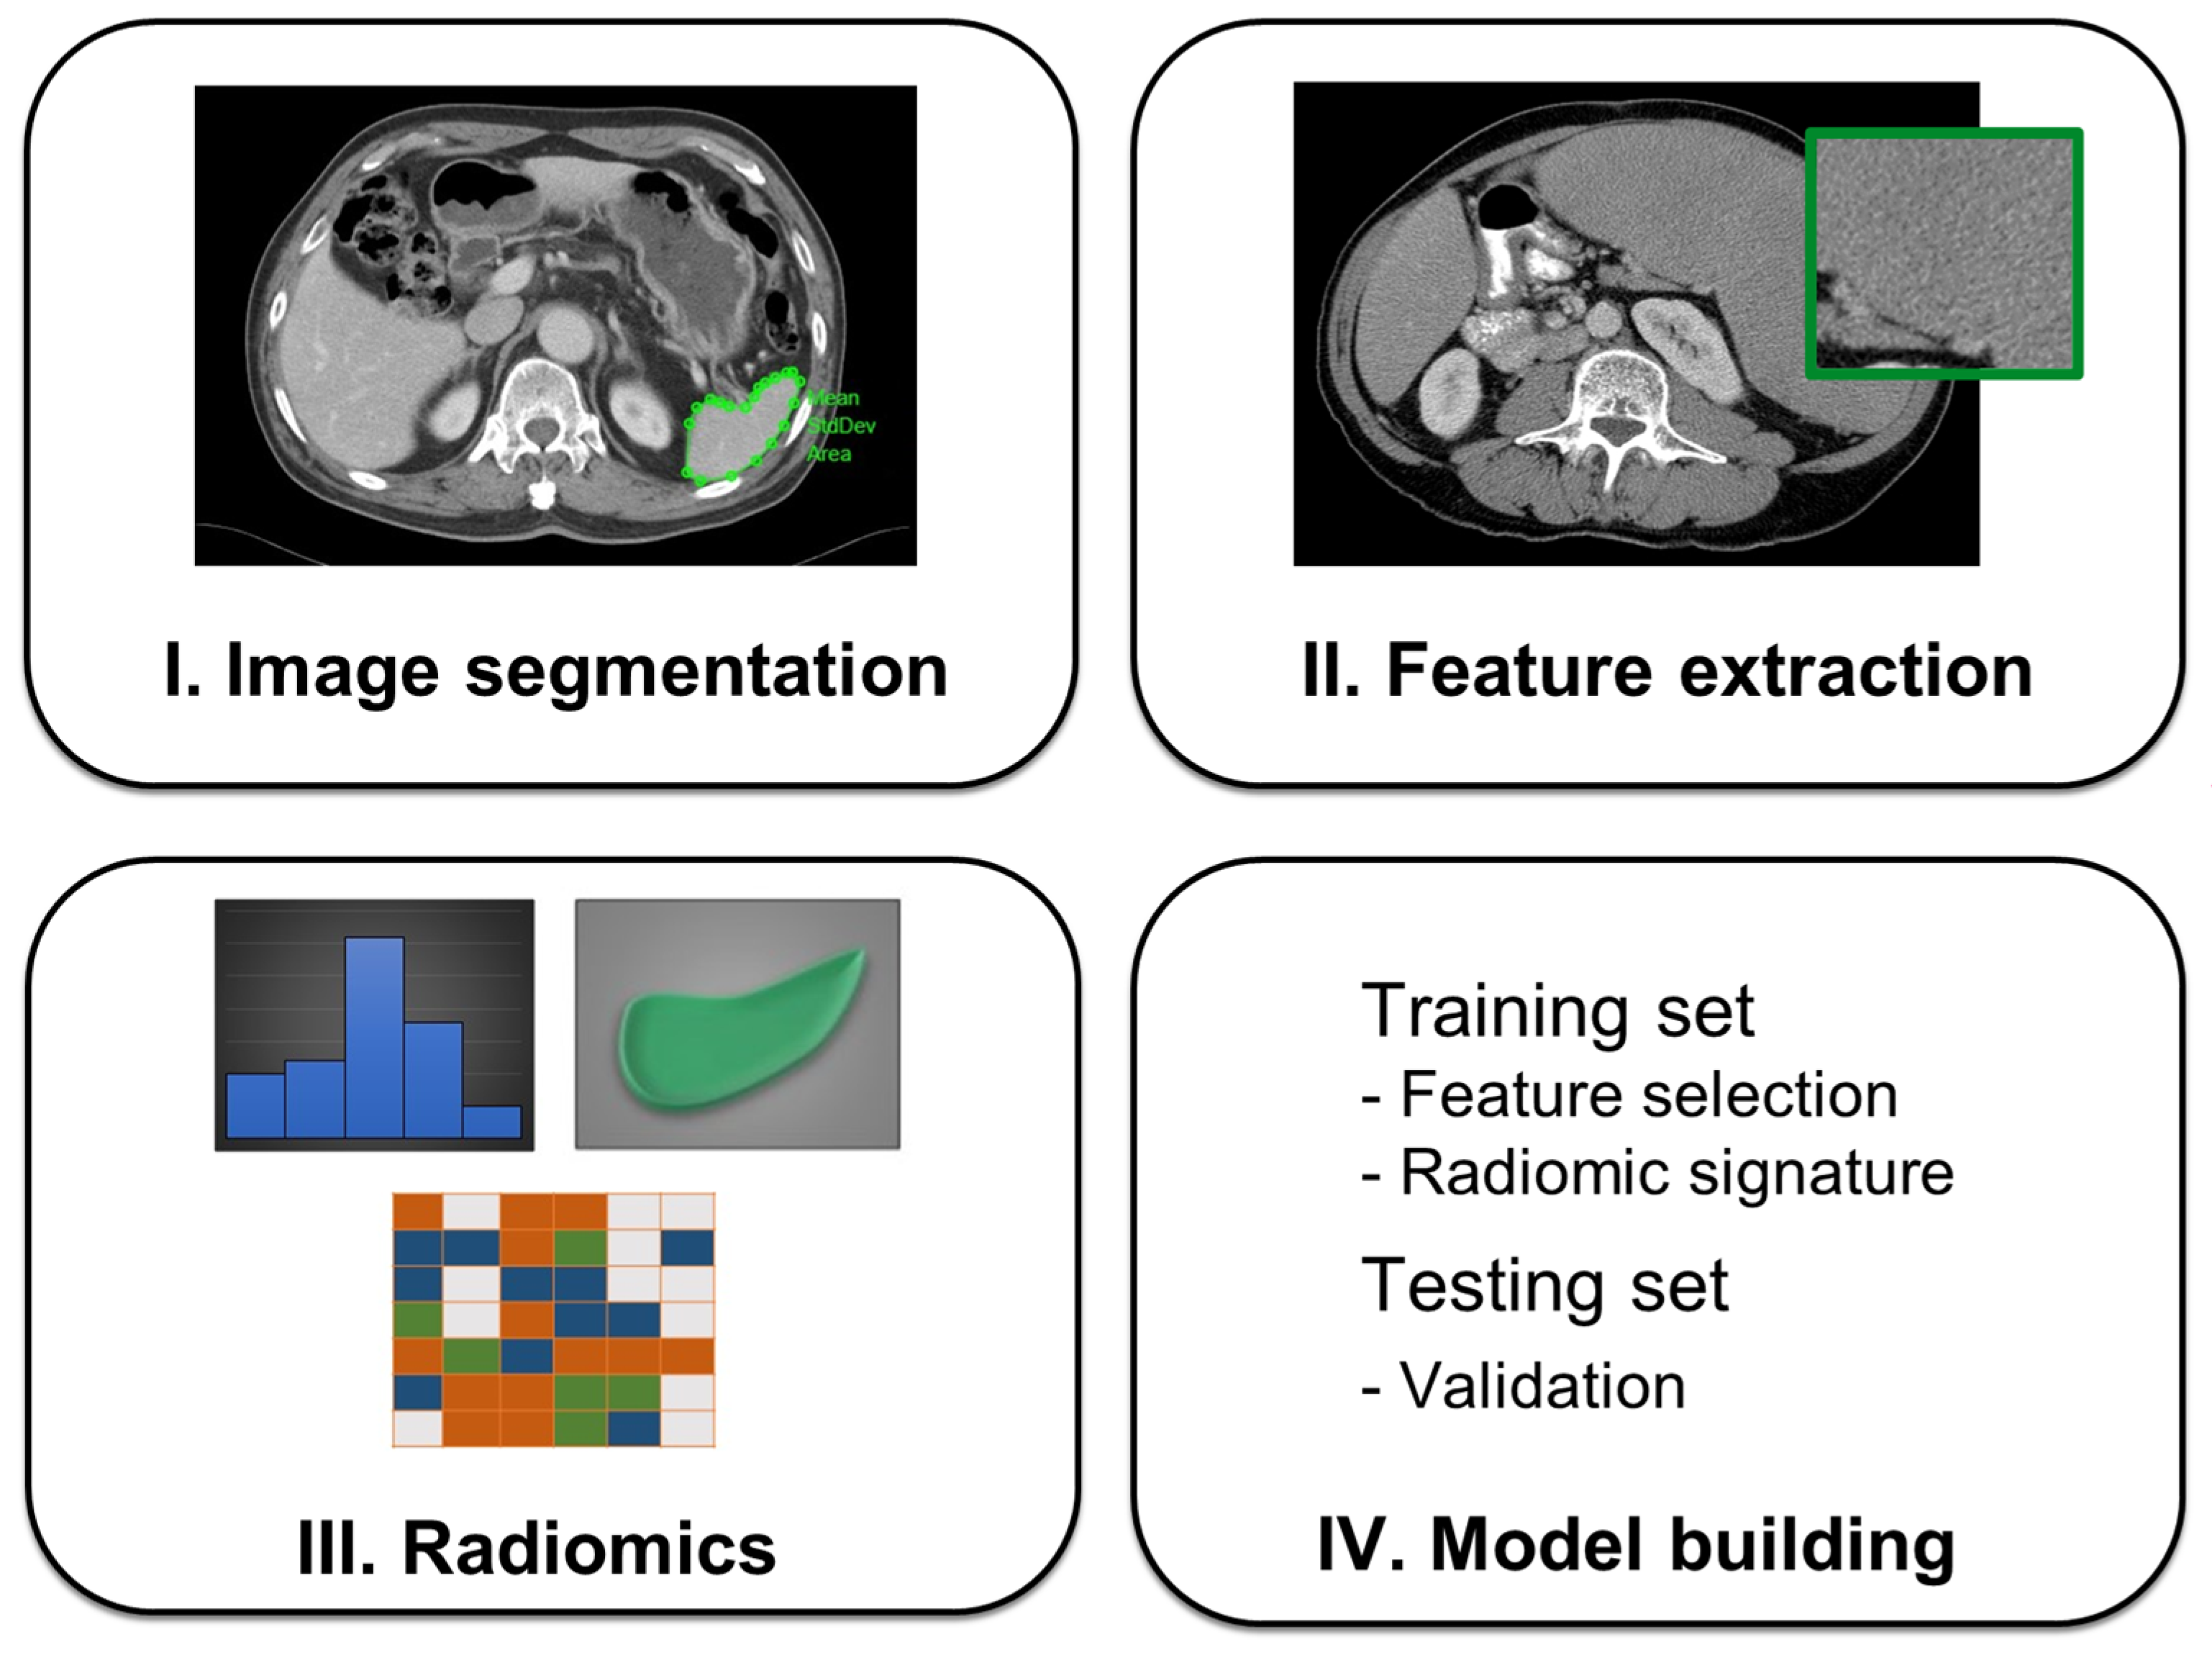

2. Related Work

3. Materials and Methods

3.3. Radiomics Feature Extraction